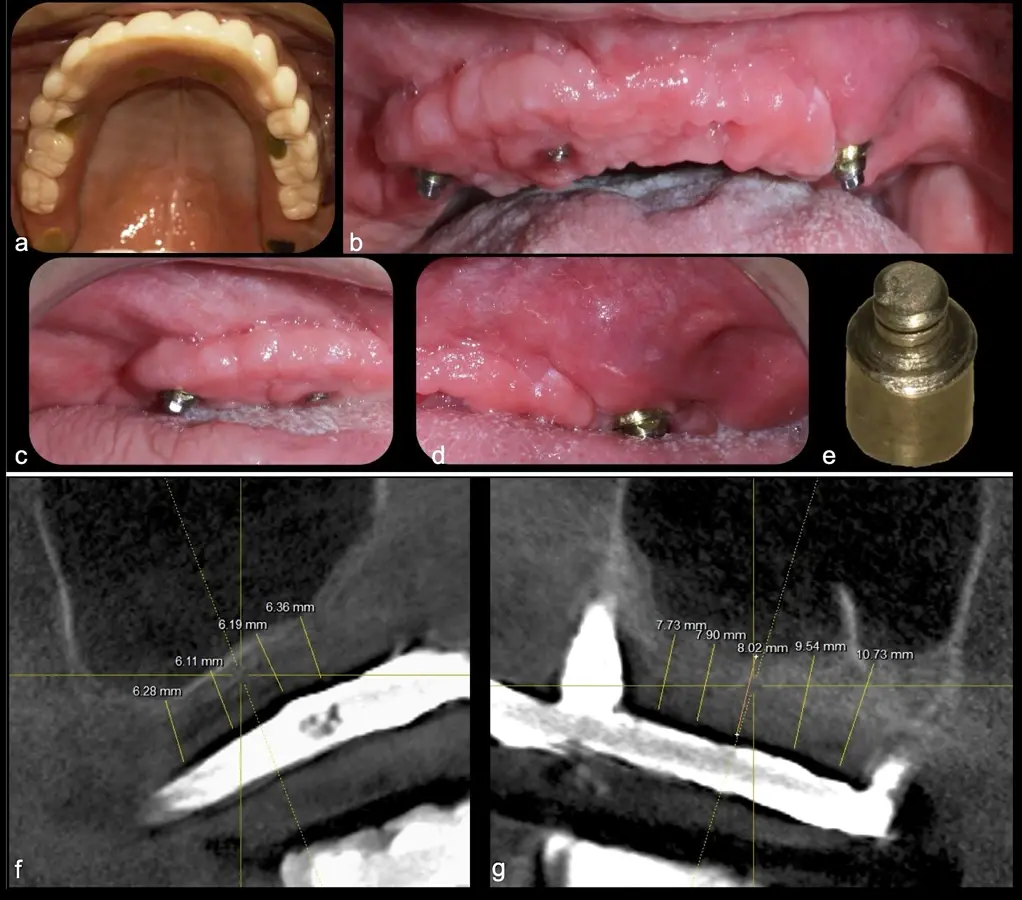

El levantamiento de piso de seno maxilar es una técnica quirúrgica aceptada previa o simultáneamente a la colocación de implantes dentales. La mayor evidencia científica refiere que si se tiene entre 0 -7 mm de altura ósea se debe realizar la elevación sinusal junto con injertos óseos; y a partir de los 8 mm, se hace más predecible la colocación simultánea de implantes dentales.1-3

Aunque esta técnica es predecible, la perforación de la membrana sinusal es la complicación intraoperatoria más común, con una prevalencia de hasta el 58.3%.4 Existen también otras complicaciones reportadas, como hemorragias asociadas a la lesión de la anastomosis arterial en el área de la pared lateral del seno maxilar.5-8

Frente a esta dificultad, a principios de este siglo se utilizó por primera vez un modelo comercial de piezoeléctrico en elevaciones sinusales demostrando su capacidad de corte sólo de tejidos duros y reduciendo el daño a la membrana sinusal, la cual cuenta con un espesor promedio de 1.13mm.10-12

El piezoeléctrico además presenta otras ventajas como una baja emisión de ruidos, vibraciones mínimas, producción de virutas óseas pequeñas, visibilidad intraoperatoria mejorada, y requiere de una incisión ósea controlada8. A nivel local, aumenta elementos pro-formadores de tejido óseo y disminuye algunas de las citoquinas proinflamatorias y resortivas en el hueso.13 Sus movimientos vibratorios durante el corte estimulan el metabolismo celular y aceleran la regeneración ósea. Además, las moléculas de oxígeno que se liberan tienen un efecto antiséptico.14,15 Por todo ello, se ha reportado que reduce la tasa de perforaciones de la membrana sinusal, el sangrado y el trauma en el área antral.16-18,19

El tipo de inserto a ser utilizado dependerá del espesor de la pared ósea. Si la pared es menor a 0.5 mm, es mejor utilizar insertos de desgaste para prevenir la ruptura de la membrana de Schneider; si el espesor es mayor a 0.5 mm, se puede utilizar insertos de corte de espesor medio (Figura 3).

El clínico puede retirar la tabla ósea o introducirla como “tienda de campaña” dentro del seno maxilar. En cualquiera de las alternativas, es importante evaluar la presencia de tabiques óseos y de la arteria postero alveolar superior.